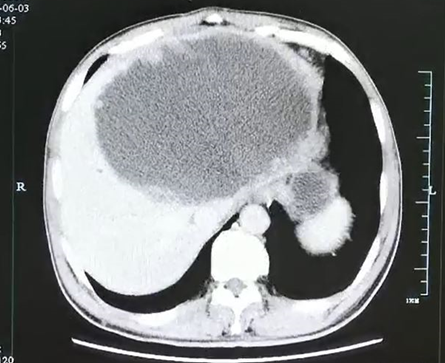

谢师傅的CT结果 杭州市一医院供图

入院后腹部CT检查发现肝脓肿壁上长了很多肿瘤样的结构,而且壁很厚。看来这个肝脓肿不简单。